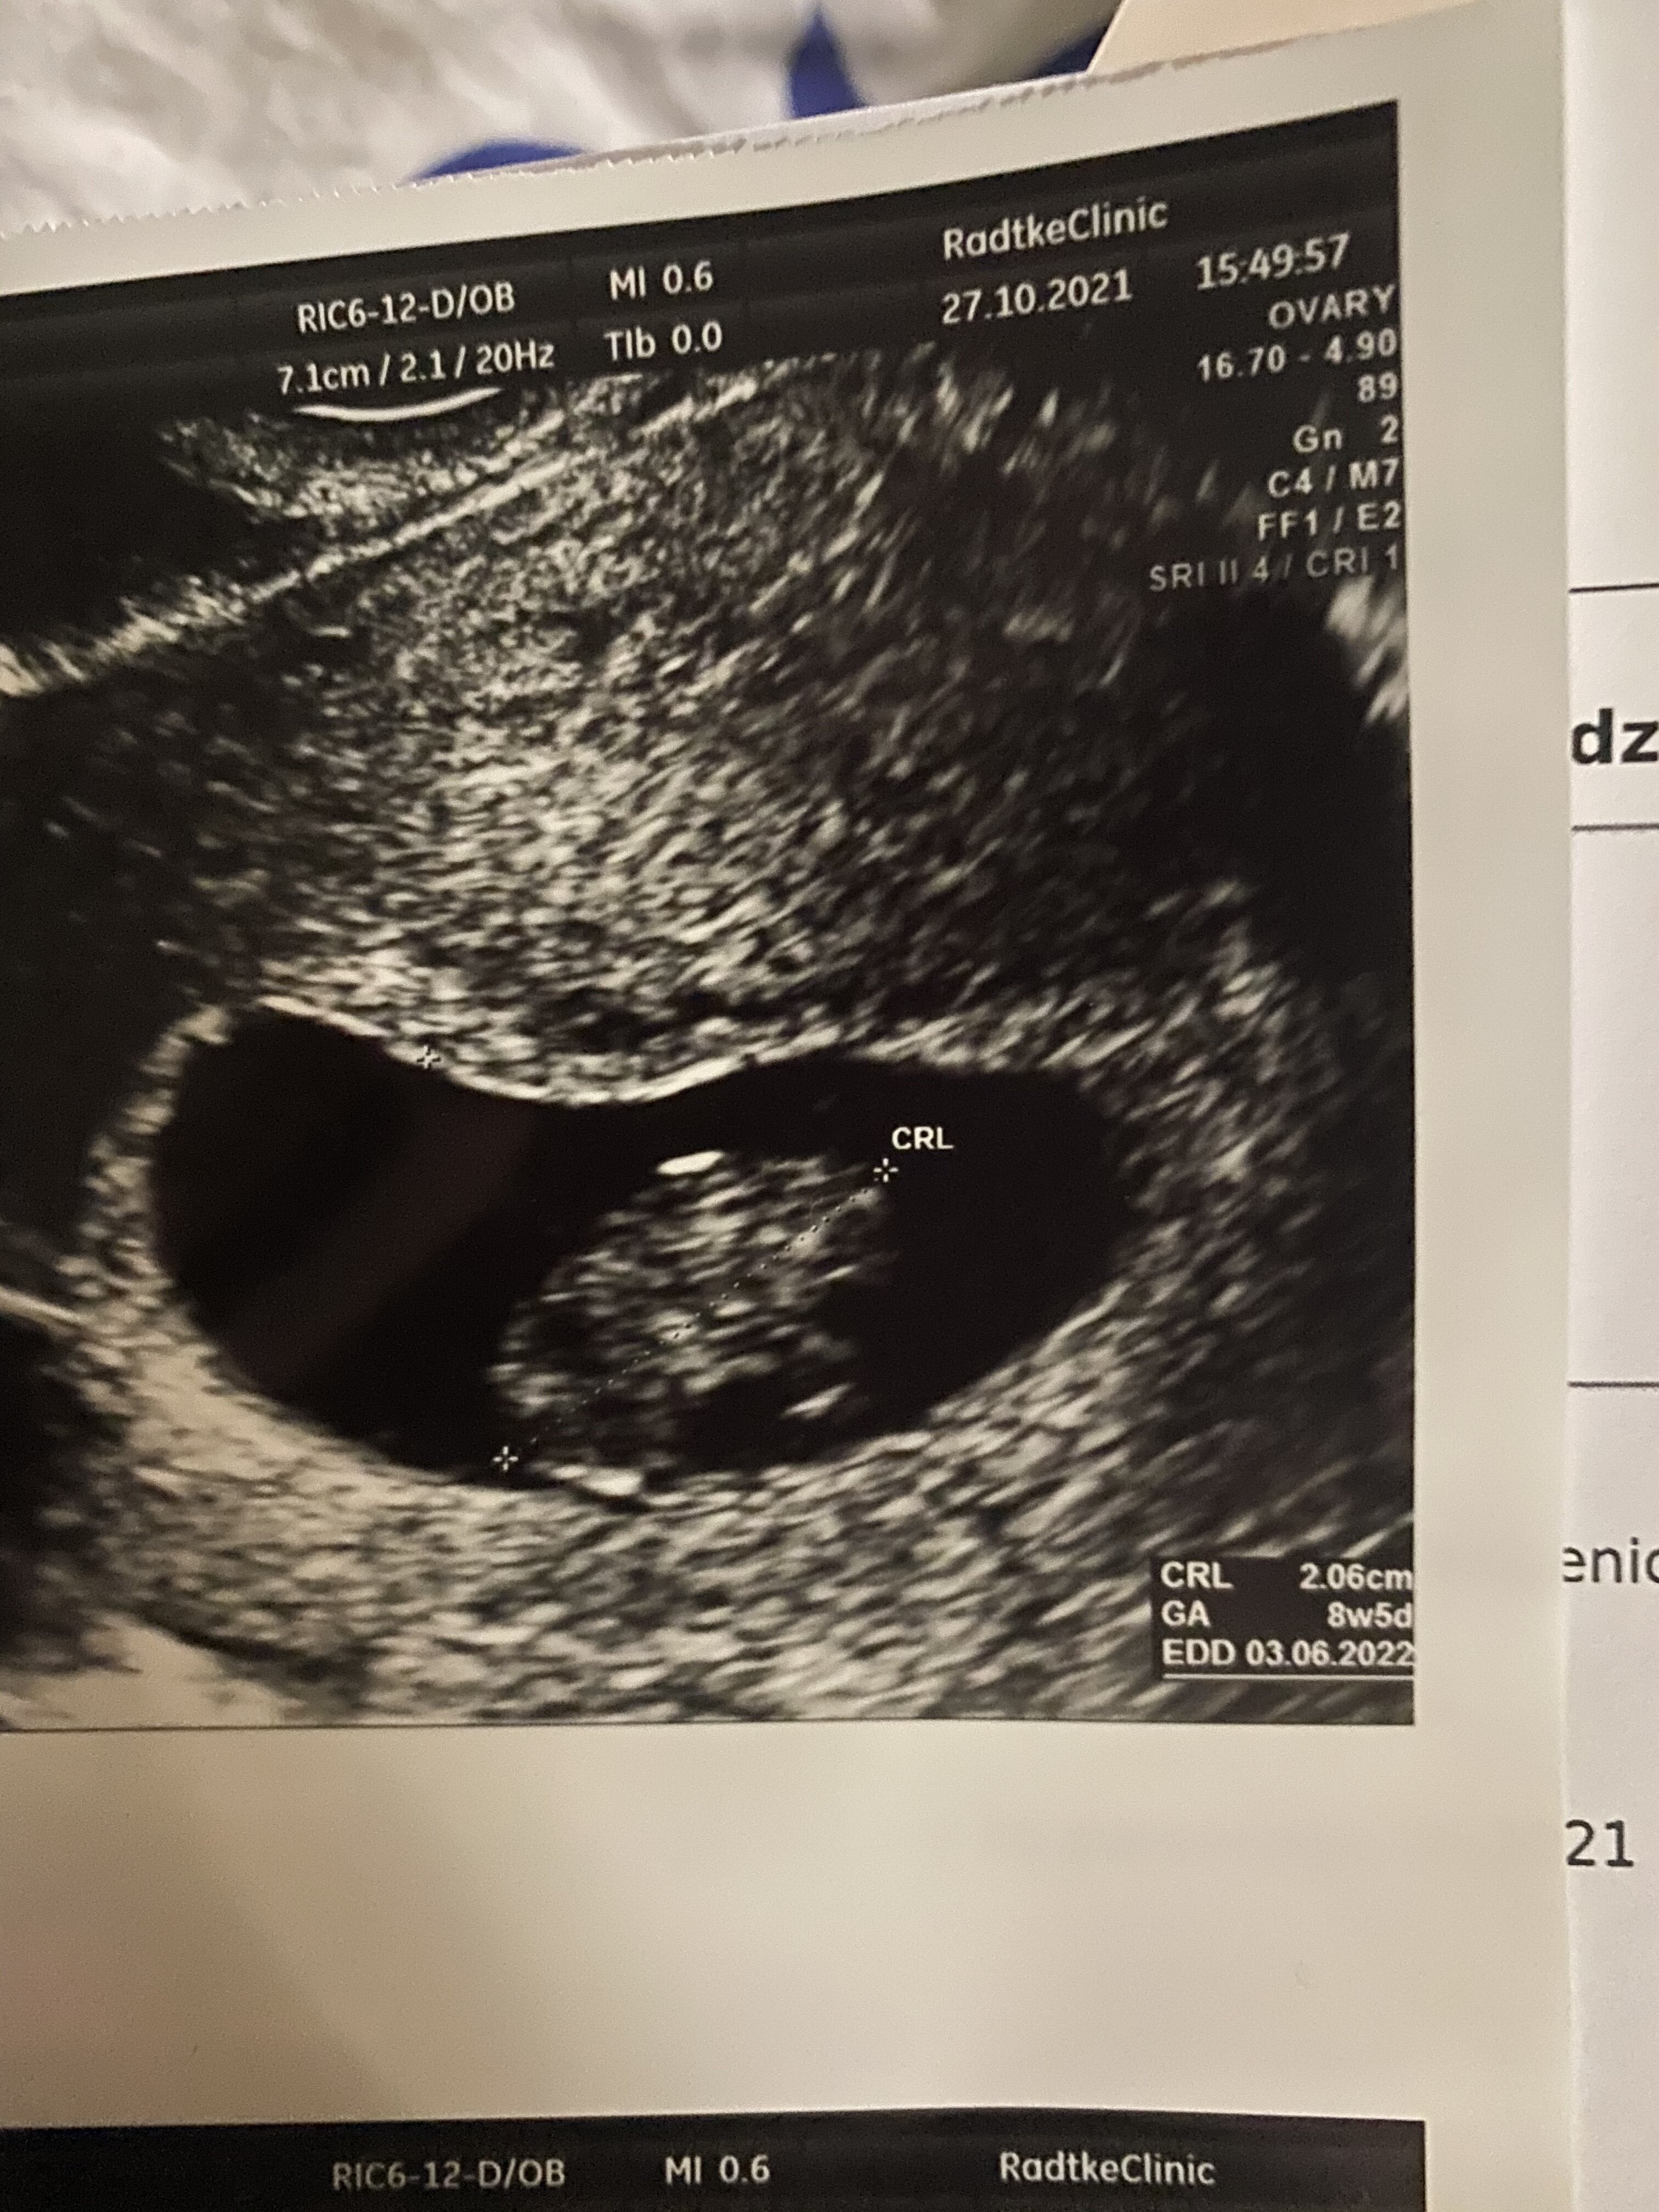

U Ciebie to chociaz zarys jakis czlowieka jest u mnie to mala plamkaJa po dzisiejszej wizycie według usg 8+5 serduszko bije i wszystko jest okej.następna wizyta 24.11 i prenatalne.

Super [emoji7] na kiedy masz termin? [emoji4]Ja po dzisiejszej wizycie według usg 8+5 serduszko bije i wszystko jest okej. [emoji3059] następna wizyta 24.11 i prenatalne.

03.06 według usg a według om 05.06Super [emoji7] na kiedy masz termin? [emoji4]